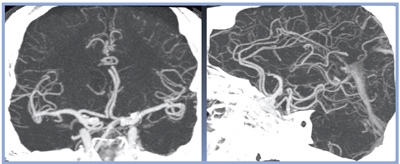

次に,頸部〜頭部CTAを施行し,3D再構成画像で,右内頸動脈の損傷が認められた。骨条件のMPR像では頸椎損傷はなく,内膜損傷のみであった(図5)。

さらにCPR画像にて,椎骨動脈の形態を評価した(図6)。

![]() 図5 症例2:右内頸動脈内膜損傷(3D再構成画像) |

![]() 図6 症例2:CPR画像 |